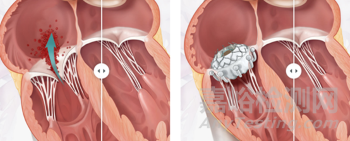

EVOQUE瓣膜是Edwards公司設(shè)計的一款自膨脹式三尖瓣瓣膜,由自膨式鎳鈦合金支架、牛心包瓣葉、編織物裙邊以及瓣葉夾持裝置組成,具有 44 、 48和52 mm 兩種尺寸型號。其固定方式主要依靠9個倒勾的瓣葉夾持件,輸送狀態(tài)時夾持件伸直,送入輸送鞘管后夾持件倒勾向心房,與自身瓣膜支架徑向支撐之間形成夾持力夾住瓣葉。操作時經(jīng)股靜脈途徑使用 28F, 多向可調(diào)彎輸送系統(tǒng)將瓣膜送至三尖瓣位置后同軸釋放。瓣膜釋放時先探出抓捕裝置以牢牢抓住瓣葉,經(jīng)位置調(diào)整后再緩慢釋放出瓣架。值得注意的是,采用此類錨定方式的人工瓣膜均對術(shù)者行瓣葉抓捕操作的能力提出了較高要求,或可通過ICE指導(dǎo)以進一步改善手術(shù)效果。

MonarQ瓣膜經(jīng)過獨特生物動力學(xué)設(shè)計,不依賴強徑向支撐力的錨定設(shè)計,以期減少術(shù)后各種并發(fā)癥如右冠擠壓、瓣葉損傷和傳導(dǎo)阻滯的發(fā)生。MonarQ瓣膜像漢堡一樣上下搭在原生瓣葉上,自然的順應(yīng)血流流動節(jié)奏,分擔(dān)收縮負荷力,在各種尺寸原生瓣環(huán)中最大限度地減少瓣周漏。”